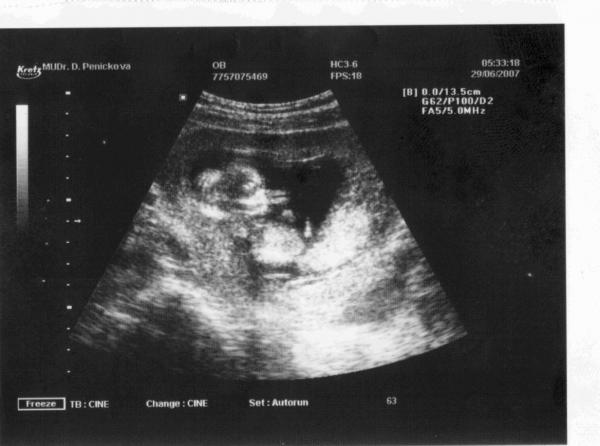

V neděli 23.9.2007 ve 20:52 se nám narodila dcerka Kristýnka, měří 50cm a váží 2,93kg. Obě děvčata jsou v pohodě a já sem šťastnej jak blecha.